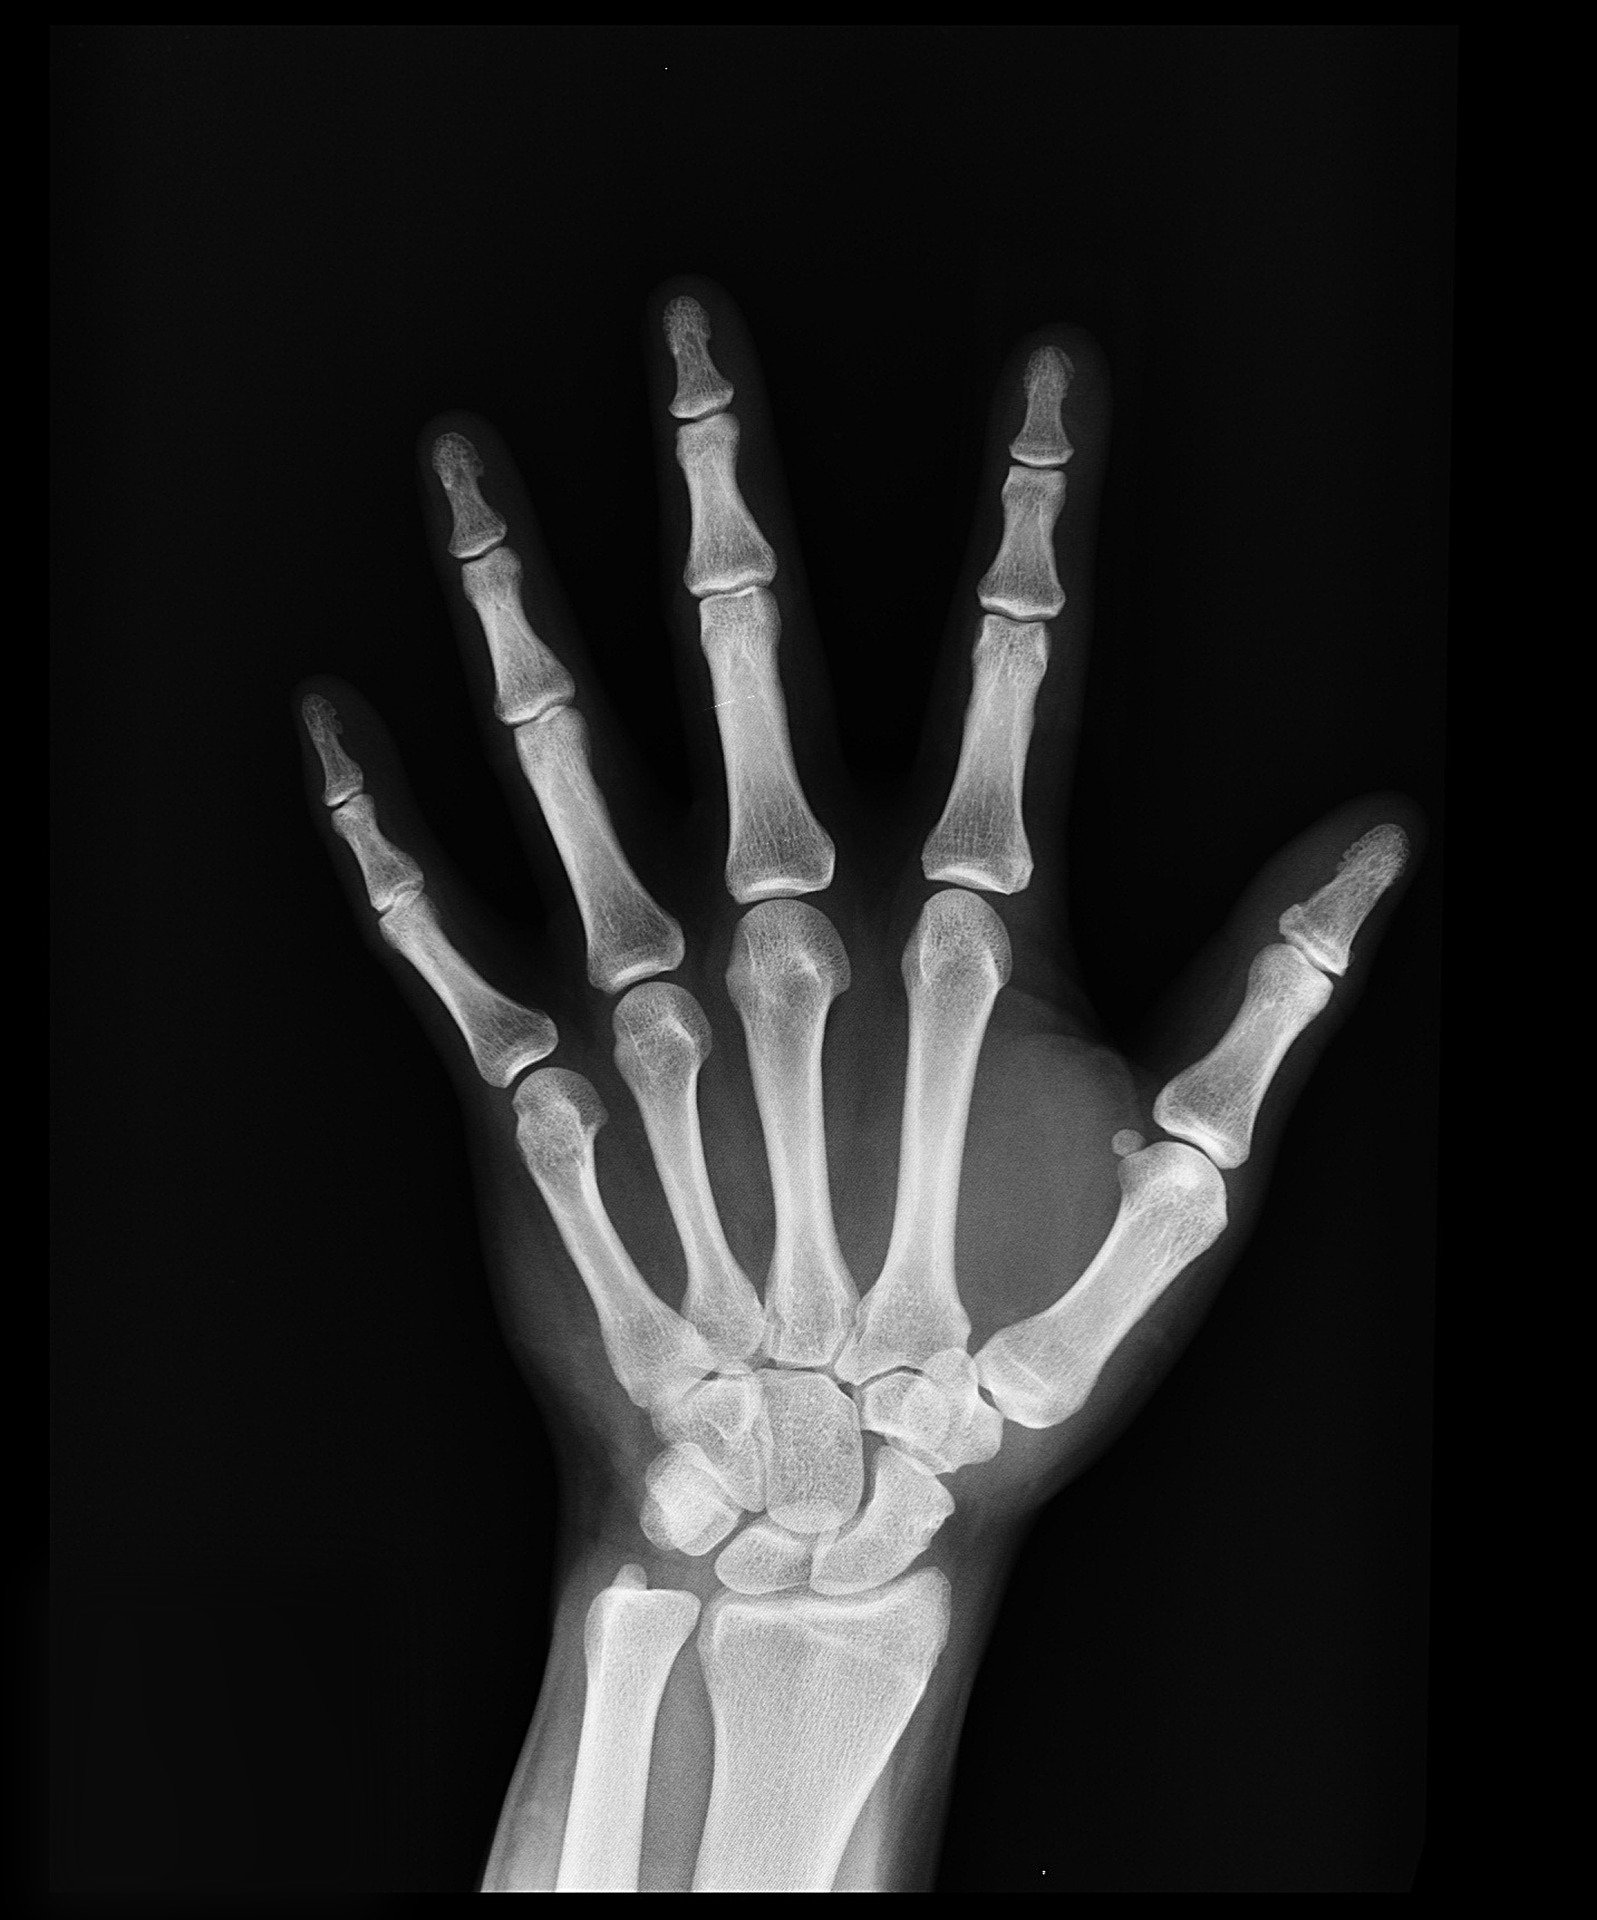

관절은 관절 연골과 인대 그리고 근육으로 구성되어 있습니다. 관절에서 소리가 나는 것은 근육의 힘줄부위놔 인대가 구부러지는 뼈를 따라가지 못하고 뼈의 결계면 바깥으로 순간적으로 어긋나기 때문입니다. 흔히 손가락에서 뼈소리가 잘 나는데 보통 뼈가 만나는 부분에는 관절사이의 마찰을 줄이기 위한 액체가 존재합니다.

뼈의 끝은 물렁뼈라고 하는 연골이 붙어있고, 연골은 주변에 얇은 피막으로 둘러싸여 있습니다. 이 막에는 윤활유 역할을 하는 액체가 들어있는데, 목이나 손가락을 움직이게 되면 이 액체는 압력을 받게 됩니다. 그리고 액체속에는 기체가 존재하게 됩니다. 액체가 압력을 받았을 시 액체속 기체가 빠져나오게 되면서 뼈에서 소리가 나는 것입니다.